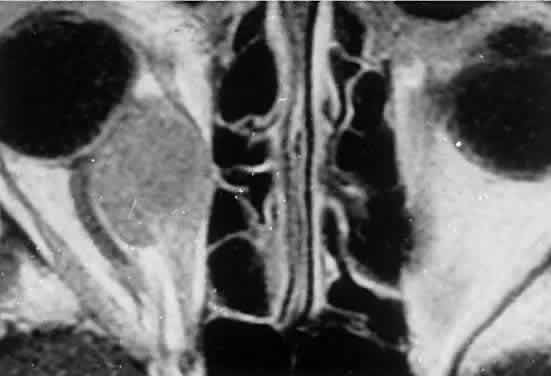

Fig. 2. MRI shows an intraconal tumor of lower intensity than the medial rectus muscle. The proximal muscle is splayed rather than compressed, suggesting that the lesion originated within the medial rectus. The diagnosis was alveolar rhabdomyosarcoma.